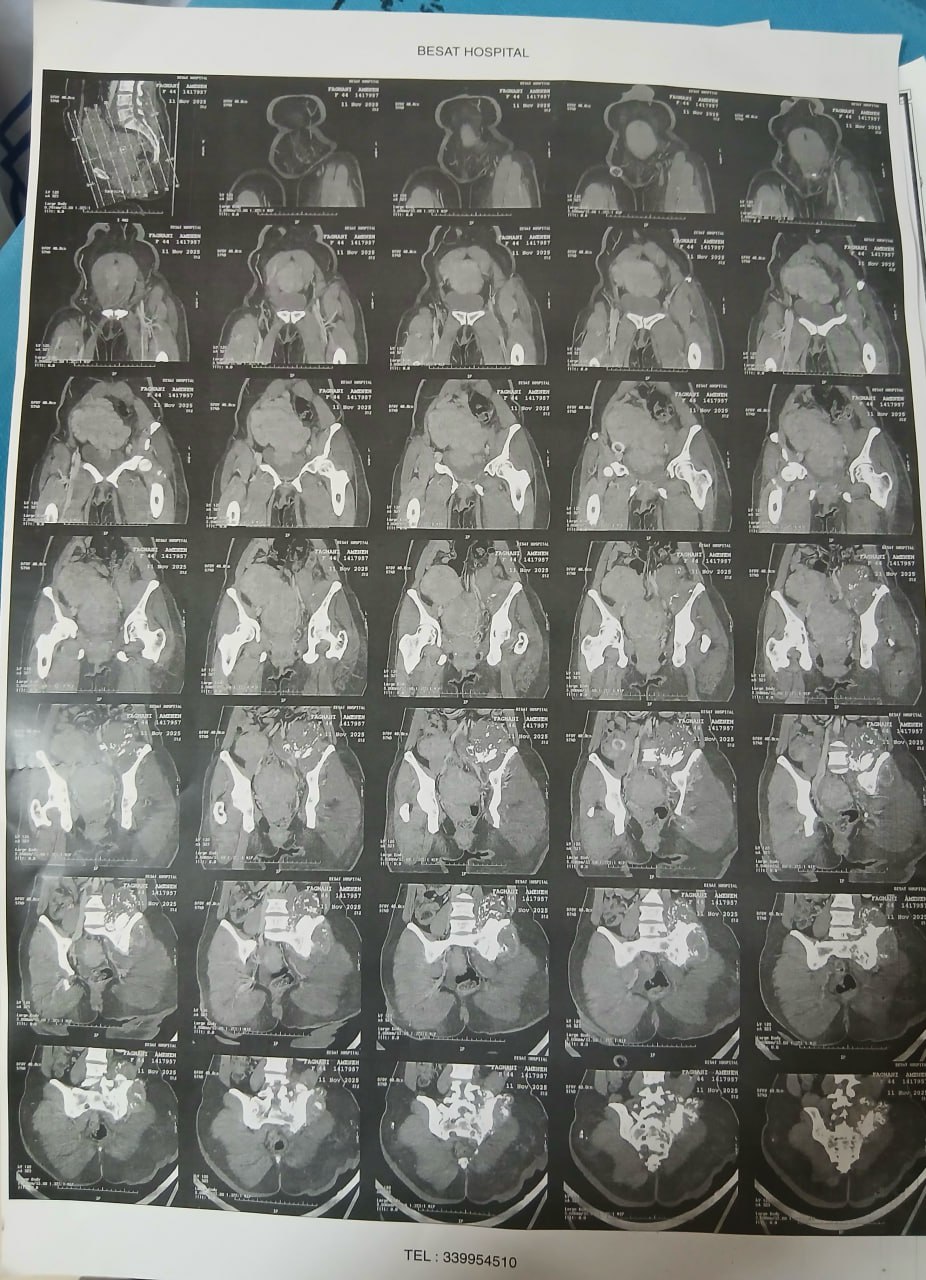

در بررسیهای تصویربرداری (MRI)،در تاریخ 24.7 ، تودهای با تشخیص کندروسارکوما همراه با DVT گزارش شده است. بیمار سابقه درد لگن داشته که شدت آن در حال حاضر نسبت به گذشته کاهش یافته است. به گفته بیمار، حجم توده در ابتدا در حدود اندازه یک تخممرغ بوده که در حال حاضر کاهش یافته است. همچنین تورم اندام تحتانی در حال حاضر نسبت به قبل کمتر شده است.

مراجعه کرده است. پس از بررسی های انجام شده در MRI انجام شده توده با درگیری مفصل ساکروایلیاک چپ و DVT؛ ابتدا تحت درمان DVT قرار گرفته است و سپس جهت پیگیری تومور رویت شده تحت بیوپسی قرار گرفته است و با تشخیص کندروسارکوما به این مرکز مراجعه کرده است و تحت کموتراپی و رادیوتراپی قرار گرفته و سایز تومور کاهش یافته است.

(تصویر مربوط به این مراجعه نیست) Other: